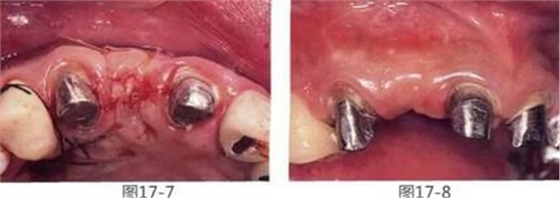

圖17-7 將羥磷灰石和結(jié)締組織填入封閉后。

圖17-8 愈合后10個月。

▲圖17-9

佩戴最終修復(fù)體時。

橋體部牙齦看上去更加自然。